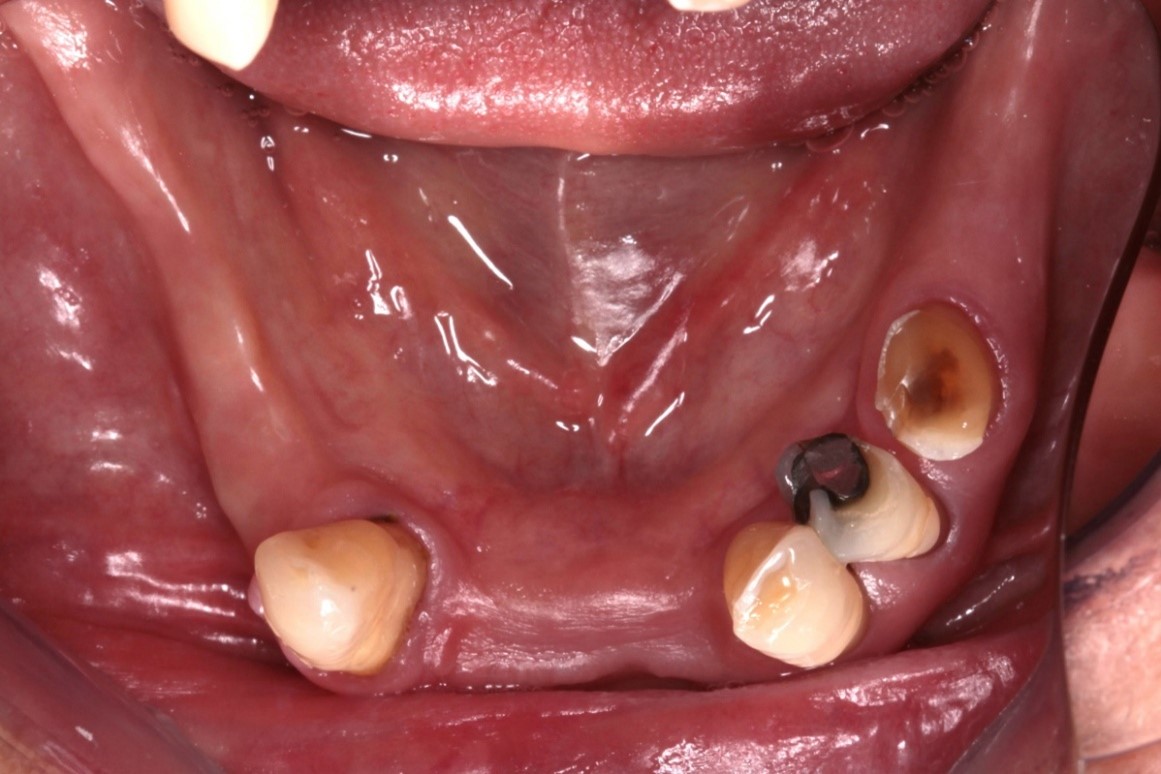

Fig. 1 e 2 – Vista oclusal

Fig. 2 – Radiografia inicial

Foram solicitados exames médicos para avaliar a condição geral de saúde do paciente. Exames de imagem iniciais foram realizados para análise detalhada do sorriso e planejamento do tratamento estético. Durante o procedimento cirúrgico, o paciente foi submetido à sedação consciente conduzida por um anestesiologista, garantindo controle da ansiedade e maior conforto.

Na análise radiográfica, constatou-se pneumatização do seio maxilar direito em direção ao pilar canino. No lado esquerdo, a extensão da pneumatização poderia inviabilizar a realização da técnica sem enxertos ósseos. Para garantir a instalação precisa e segura do implante, foi realizado um acesso lateral à janela do seio maxilar, permitindo o tratamento da parede anterior do seio com uma sonda para determinar a posição ideal do implante distal. Aproveitou-se o máximo de osso disponível, tangenciando o seio maxilar e eliminando a necessidade de enxertos ósseos. Foi escolhido o sistema Vezza da FGM, devido a geometria que fornece alta estabilidade primária e oferece conexão hexagonal externa universal, ou seja, bastante versátil.